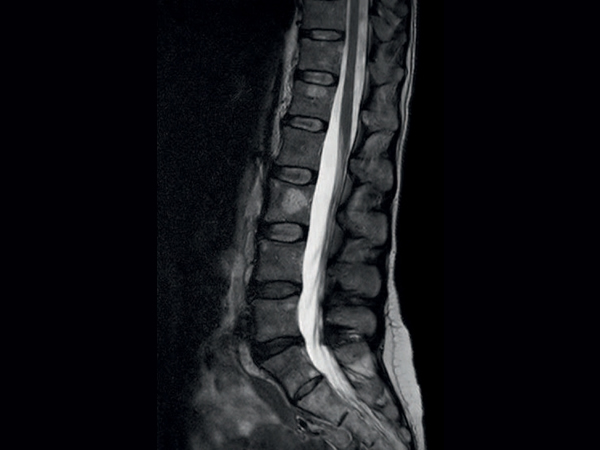

Comprehensive Lumbar Spine imaging at 1.5T

Meander Medical Center, Amersfoort, The Netherlands